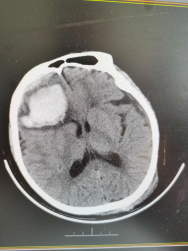

患者女性,82歲,既往有高血壓、心臟病及慢阻肺病史;同時合并快速型房顫,長期口服抗凝藥物。因不慎跌倒致頭痛急診入院。入院診斷為重型閉合性顱腦損傷,右額葉腦挫裂傷伴腦內(nèi)血腫,雙側(cè)急性硬膜下出血,枕骨骨折,創(chuàng)傷性蛛網(wǎng)膜下腔出血。

患者術(shù)前和術(shù)后頭顱CT,顱內(nèi)血腫完全清除